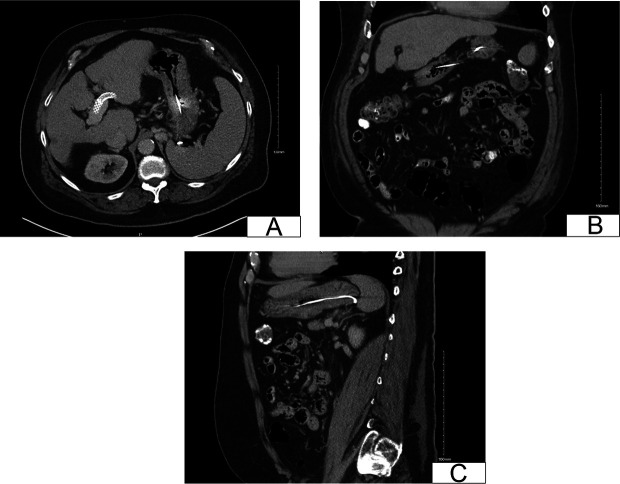

Gastric varices are a severe complication of portal hypertension and may lead to life-threatening bleeding. Endovascular interventions, including transjugular intrahepatic portosystemic shunt and coil embolization, are effective treatment strategies. However, coil migration is a rare but serious complication. We present a unique case of coil migration from a gastric varix to the duodenum after transjugular intrahepatic portosystemic shunt and embolization.

Abstract Image